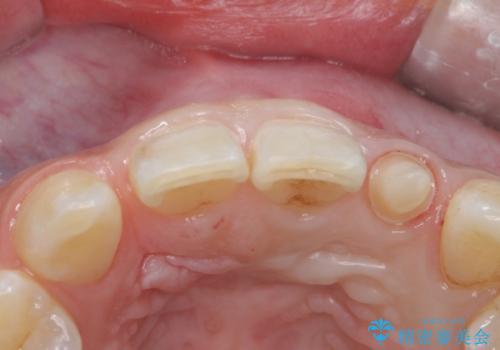

- 左上の前歯の変色が気になるとのことで来院されました。

もともと小さい歯(矮小歯)に樹脂が盛り足されている状態でした。

今後の変色をなくすために樹脂ではなくセラミックでの治療を行います。